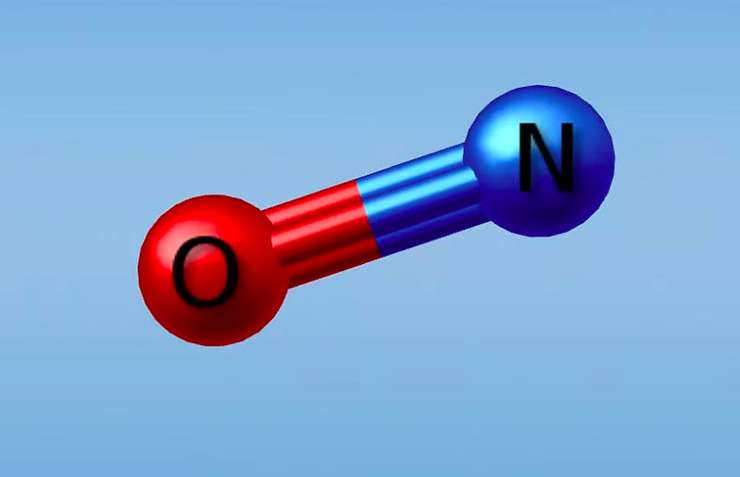

Многие даже не догадываются, какую важную роль в организме человека играет оксид азота

Когда мы задумываемся о том, как бы укрепить свое здоровье, то в первую очередь в голову приходят витамины и микроэлементы. Они и правда важны, ведь их прием помогает оставаться энергичными и не болеть. Вместе с тем человеческий организм и сам способен вырабатывать различные вещества, чтобы поддерживать свою работу. По словам профессора и доктора наук Ихора Хука, врача Венской Частной Клиники, важную роль в организме человека играет оксид азота. И чем больше этого элемента в теле, тем крепче иммунитет и меньше вероятность сердечного приступа.

В 1998 году американскому фармакологу Луи Игнарро и его двум коллегам вручили Нобелевскую премию за открытие молекулы оксида азота. Ученые выяснили, что эта молекула продуцируется в человеческом теле и имеет отношение почти ко всем метаболическим и физиологическим процессам — она управляет как внутриклеточными, так и межклеточными процессами. Многие болезни — гипертония, ишемия миокарда, тромбозы, рак — вызваны нарушением физиологических процессов, которые регулирует окись азота. Оксид азота обеспечивает кровью органы (легкие, печень, почки, желудок, мозг, сердце), тем самым влияя на их функции. Каждый орган имеет кровеносные сосуды и благодаря им эта молекула проникает во все точки организма и поддерживает его здоровье.

Тем временем эту молекулу нельзя купить в магазине — в чистом виде она существует лишь в организме человека. По словам доктора Игнарро, данный летучий газ, который является очень нестойким соединением, вырабатываясь в нашем организме, существует очень короткое время и распадается. Именно поэтому все, что мы можем, — это стимулировать выработку оксида азота. Сейчас оксид азота указывает направление поиска и создания лекарственных средств от множества самых разных болезней.

Как уже было отмечено, многие даже не подозревают о важности оксида азота для организма. Профессор, дважды доктор наук, специалист Венской Частной Клиники Ихор Хук подтверждает это. «Даже мои студенты учатся по устаревшим учебникам. Когда я спросил их, какой элемент в нашем организме играет самую важную роль, 99% из них ответили, что это кислород», — посетовал доктор Хук. Между тем научному сообществу уже в течение последних двадцати лет известно, что таким элементом является оксид азота — сердце продолжает биться, даже если доступ к кислороду перекрыт, а вот без оксида азота сердечная мышца тут же прекращает качать кровь. Врачи призывают всех начинать заботиться о своем здоровье как можно раньше, ведь сердечный приступ — это не внезапно возникнувшая беда, а результат проблем, постепенно накапливающихся с молодости.